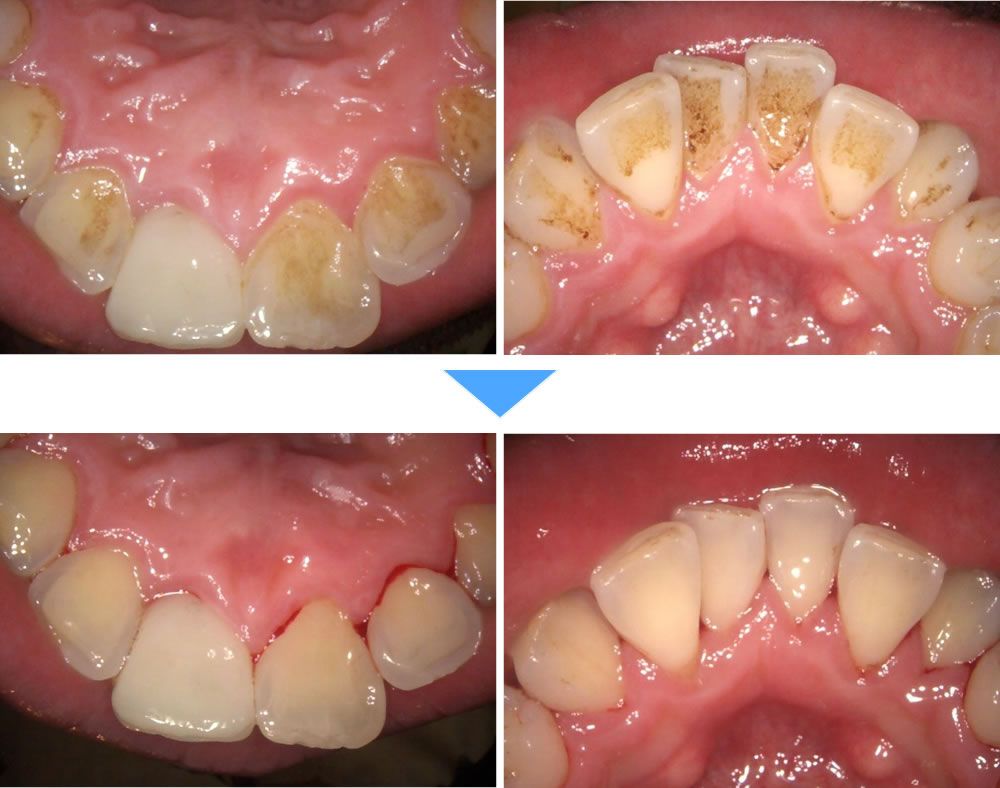

下顎前歯部に縁上歯石、全額的に縁下歯石の沈着の歯周病治療症例

年齢

30代

性別

男性